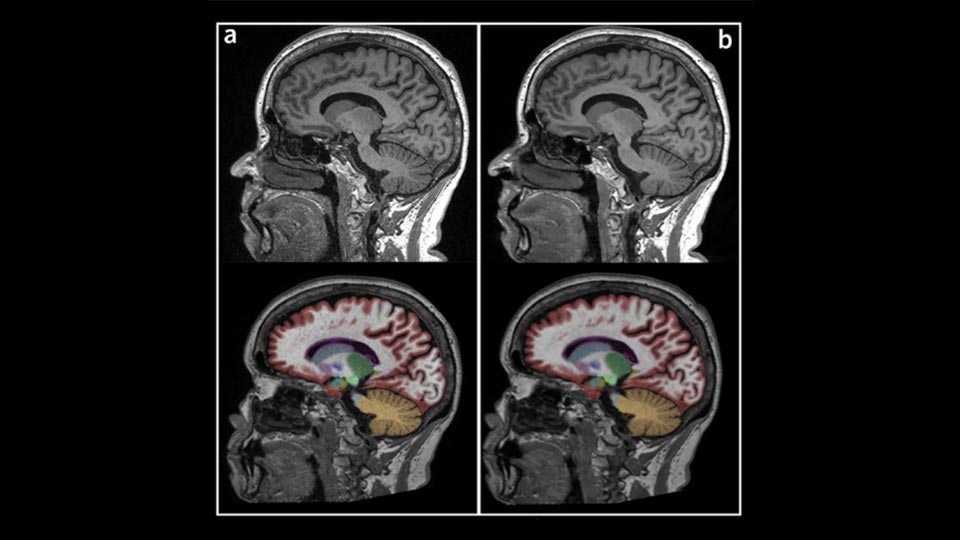

With GE HealthCare MR and PET/MR imaging equipment, you can be confident in having robust solutions for AD patient management.